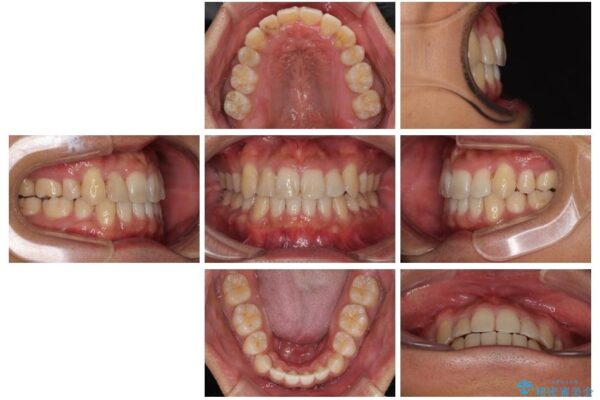

治療後について

八重歯はきれいに整い、前歯もバランスよく収まり、横顔のラインも自然に改善されました。

治療後、患者様は「思い切り笑えるようになった」と大変喜んでくださいました。

治療後

• 八重歯と前歯のガタガタを抜歯矯正で治療|クリアブラケット使用例 治療後画像